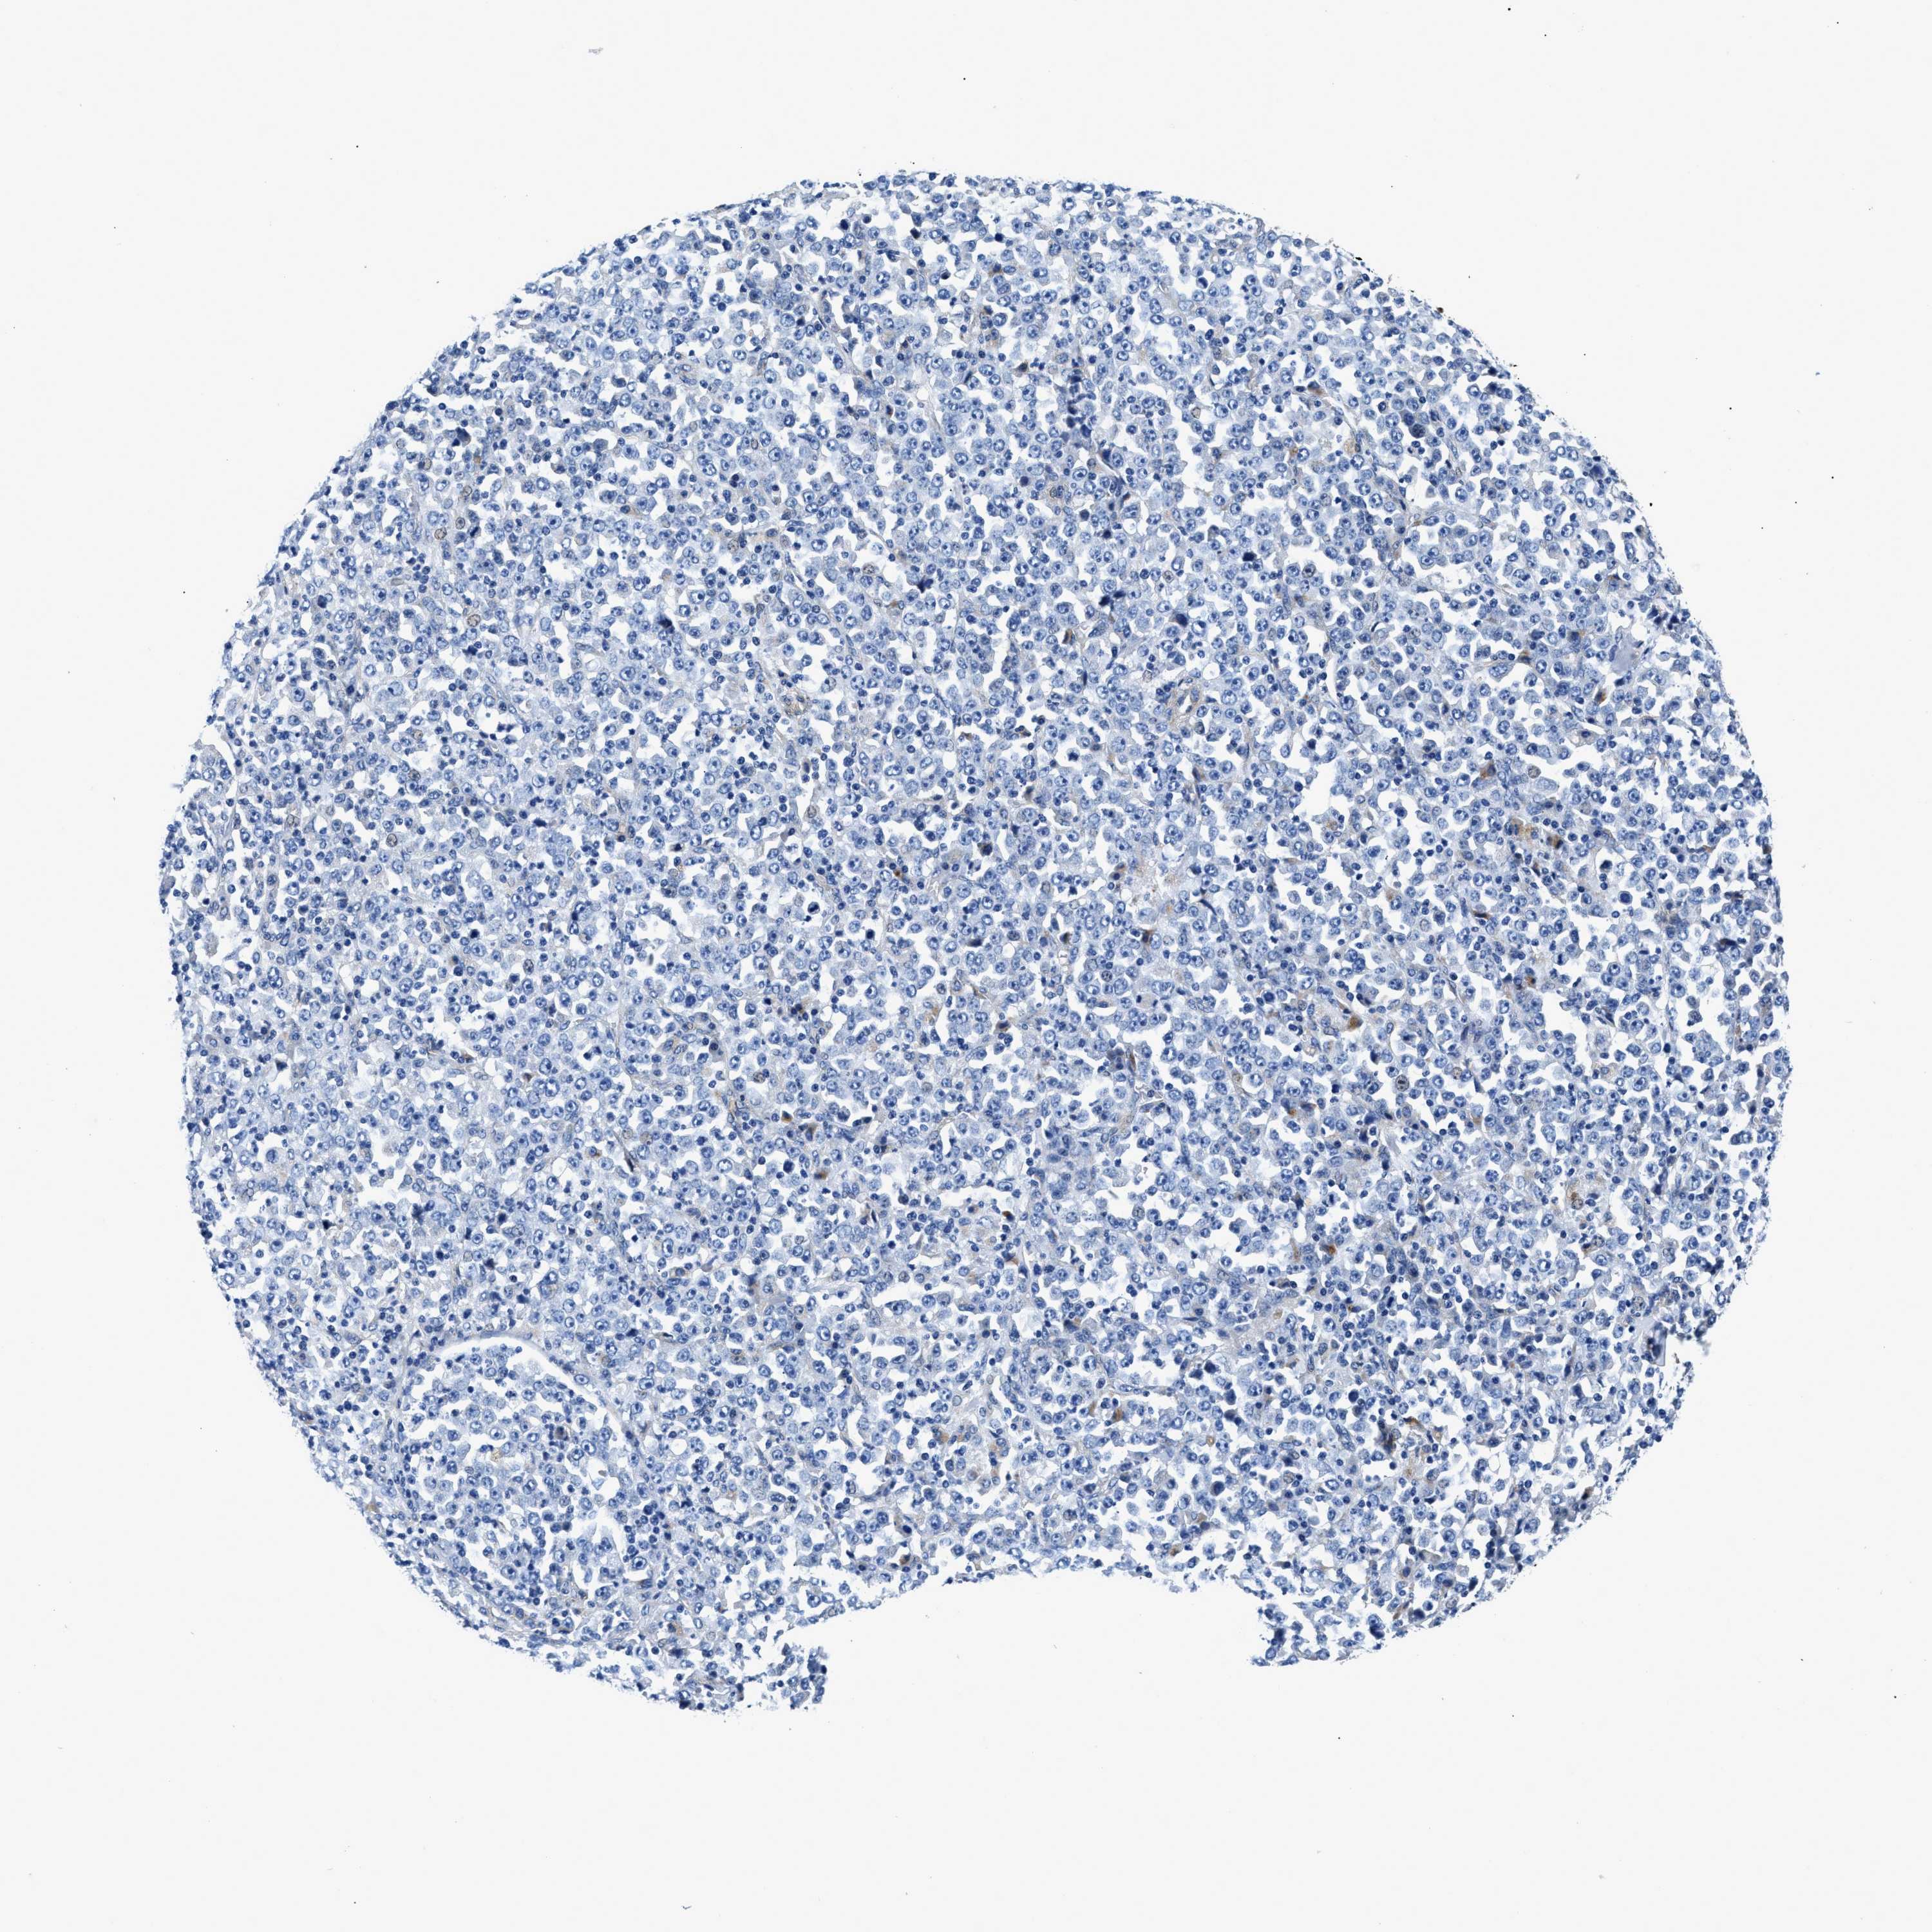

STOMACH CANCER - Protein expressioni

A mouse-over function shows sample information and annotation data. Click on an image to view it in a full screen mode. Samples can be filtered based on level of antibody staining by selecting one or several of the following categories: high, medium, low and not detected. The assay and annotation is described here.

Note that samples used for immunohistochemistry by the Human Protein Atlas do not correspond to samples in the TCGA dataset.

Antibody stainingi

Antibody staining in the annotated cell types in the current human tissue is reported as not detected, low, medium, or high, based on conventional immunohistochemistry profiling in selected tissues. This score is based on the combination of the staining intensity and fraction of stained cells.

Each image is clickable and will lead to virtual microscopy that enables deeper exploration of all samples and also displays staining intensity scores, fraction scores and subcellular localization as well as patient and tissue information for each sample.

Antibody CAB001960

Antibody CAB016353

Staining

High

Medium

Low

Not detected

Intensity

Strong

Moderate

Weak

Negative

Quantity

>75%

75%-25%

<25%

None

Location

Nuclear

Cytoplasmic/membranous

Cytoplasmic/membranous,nuclear

Adenocarcinoma, NOS

Adenocarcinoma, High grade